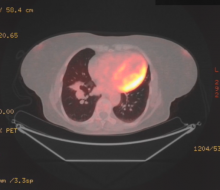

Here, the authors describe the safe and effective use of a GelPOINT Alexis® wound retractor (Applied Medical) during a thoracoscopic CO2-aided advanced pulmonary resection. The procedure carried out was a right lower bilobectomy for non-small cell lung cancer (NSCLC).

The authors applied a two-port anterior approach, using a 3 cm incision for the utility port at the level of the fourth intercostal space in the anterior axillary line and a further 1 cm incision at the level of the seventh intercostal space in the anterior axillary line. The GelPOINT wound retractor was inserted at the utility port, and it allowed the use of enhanced view and increased surgical space from CO2 insufflation together with the advantages of a 3 cm incision. The postoperative course was uneventful and the patient was discharged home on day two after surgery. Histology confirmed a fully-resected T2aN1 R0 NSCLC adenocarcinoma.